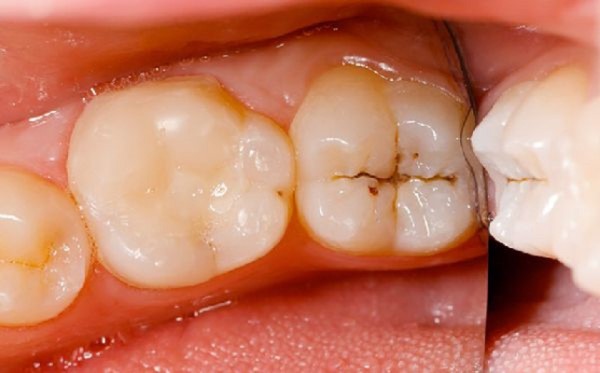

Trong giai đoạn đầu, nang chân răng thường chỉ gây ra những thay đổi rất tinh tế về màu sắc của răng, đặc biệt ở phần chân răng. Tuy nhiên, dấu hiệu này khó nhận biết và dễ bị bỏ qua, dẫn đến việc chậm trễ trong điều trị. Khi nang phát triển lớn hơn, các triệu chứng rõ ràng hơn sẽ xuất hiện, bao gồm:

Trên phim X-quang, nang chân răng thường xuất hiện dưới dạng một vùng sáng hình oval hoặc tròn, dính liền với chân răng đã bị chết tủy. Răng thường có lỗ sâu, rộng; vùng chóp răng nằm trong khu vực thấu quang, và dây chằng quanh răng bị giãn rộng.